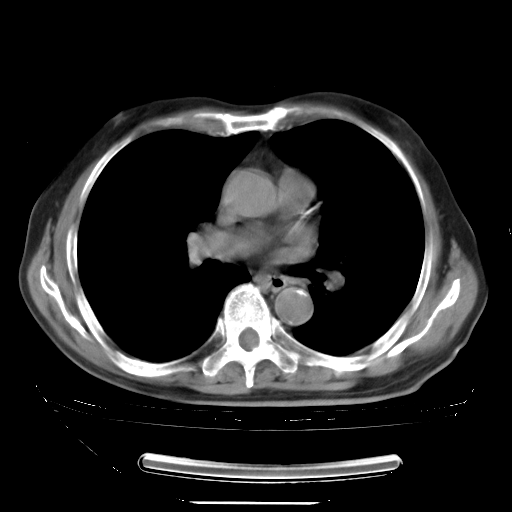

今天复查肺部CT,发现双肺广泛磨玻璃样改变。所以我把3月19日和5月9日相隔50天的肺部CT上传。请大家会诊。

2009年3月19日肺部CT片。

2009年3月19日肺部CT